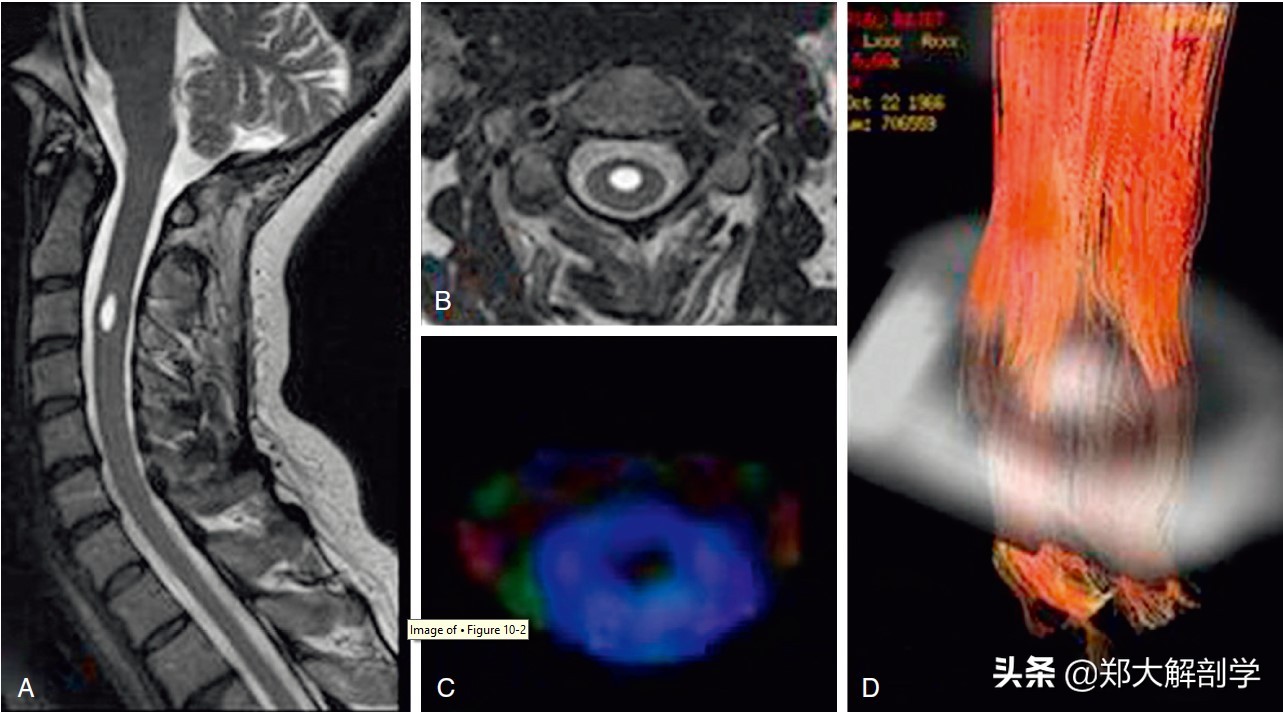

脊髓空洞症患者,MRI矢状位(A)和轴位(B)T2加权像显示在C3水平有一个中央型脊髓空洞。C,轴位的彩色各向异性分数图未见穿过病灶区域的神经纤维束。D,纤维跟踪成像显示空洞轴位神经纤维的移位。脊髓室管膜瘤也会同样的影响学表现。相比之下,脊髓星形细胞瘤可见浸润或较细的神经纤维穿过病灶。